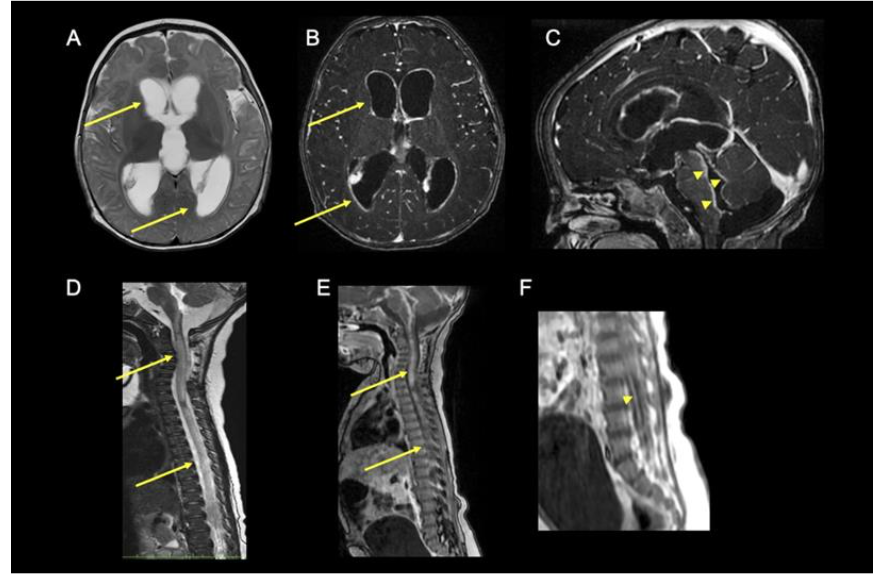

In ANEC/ANE1, there is involvement of bilateral thalami in the form of areas of diffusion restriction with haemorrhagic necrosis (‘trilaminar sign’). Involvement of midbrain, brainstem and cortex are also noted and have been associated with poorer outcomes. In milder forms of sporadic ANE, spontaneous resolution of lesions with residual hemosiderin deposits are noted with minimal sequelae.

Fig 5 (A–F) – Acute necrotising encephalopathy of childhood (ANEC) in a 12-month-old child with viral gastroenteritis 2 days prior to rapid decline in sensorium. Classical ‘Trilaminar’ sign (arrow) noted in the T1 (A) and T2 (B–D) axial images in bilateral thalamic, hyperintensities also present in cerebellum and periventricular regions with restricted diffusion on DWI (E) and blooming on SWI (F) (s/o micro-hemorrhages). MR spectroscopy did not show inverted lactate doublet. FIRES is usually associated with normal imaging at the outset. Some cases show swelling in the mesial temporal or hippocampal regions presumably from prolonged seizure activity. Late scans show diffuse cortical atrophy due to a combination of brain injury and use of prolonged steroids.